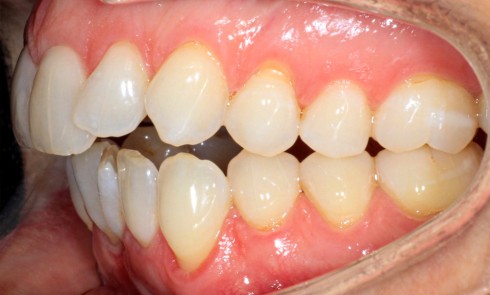

Article réservé à nos abonnés Les vrais critères de choix de la Dimension Verticale d’Occlusion thérapeutique : applications cliniques

À travers trois situations cliniques différentes, illustrées par une anamnèse, des examens cliniques et radiologiques, une réflexion est engagée pour...